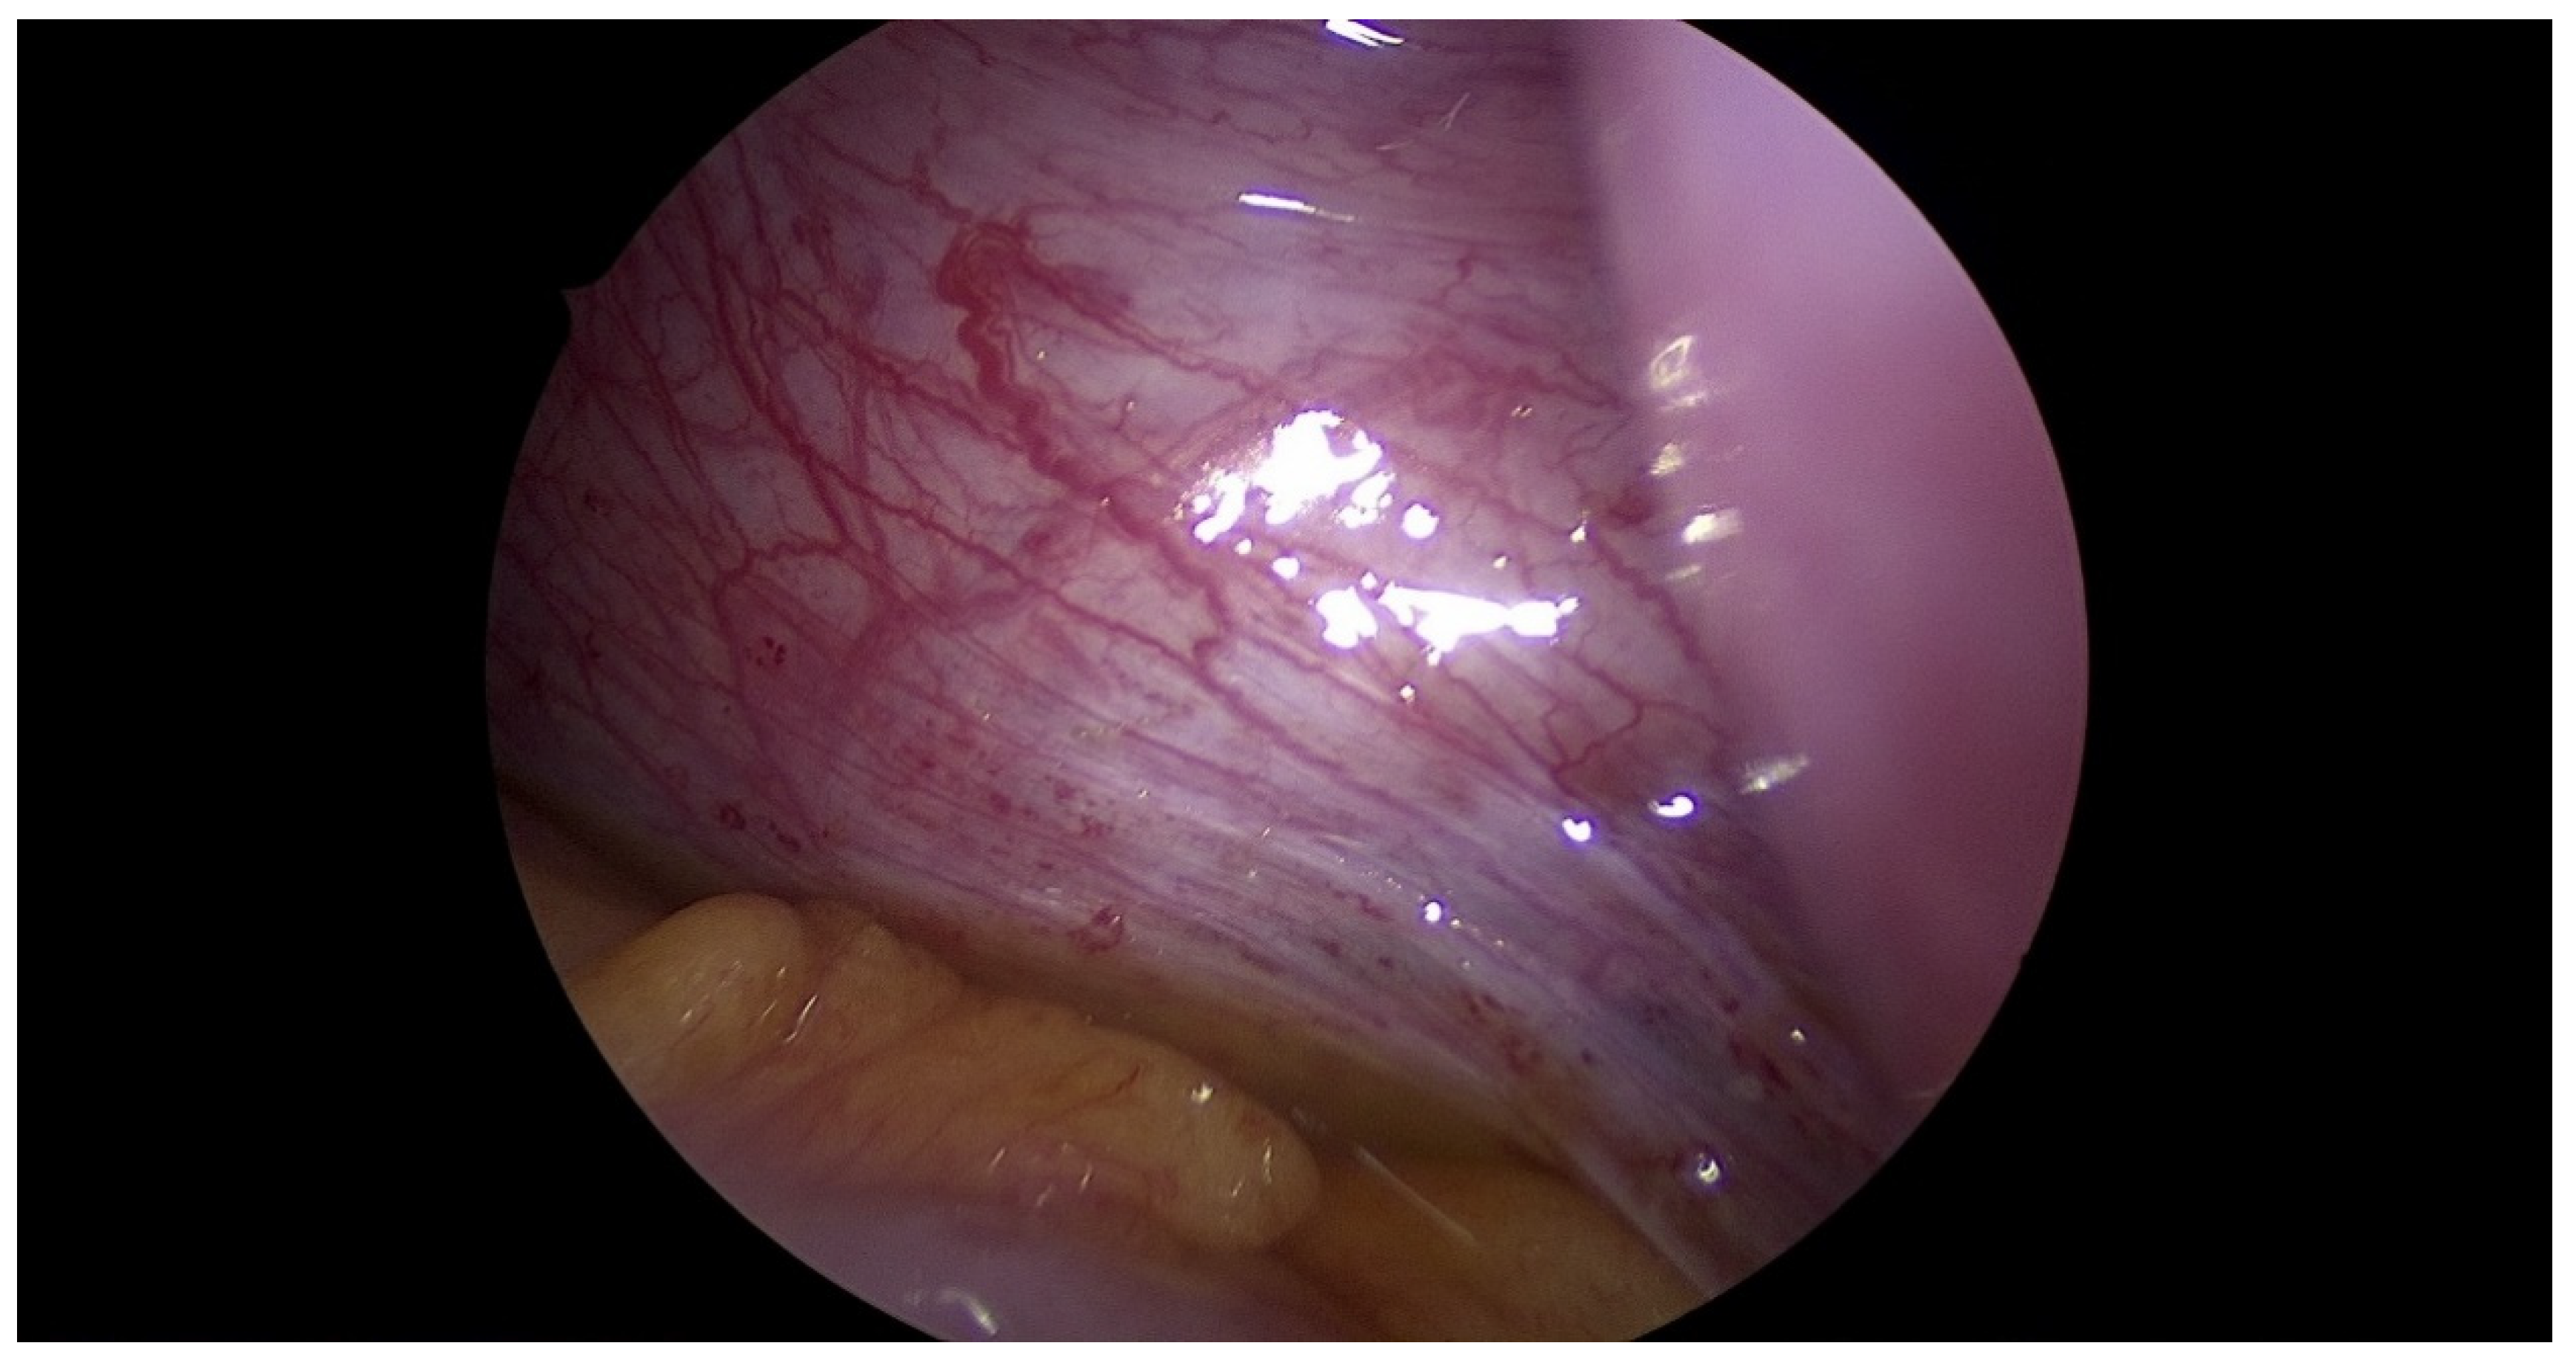

2.3. Surgical Technique

| Step 3. Surgical management Surgery is necessary when acute abdominal symptoms are present. “Wait and see” approach is only possible when the clinical situation allows it. Perform laparoscopy and vaginoscopy in order to achieve the correct diagnosis and treat concomitant hematosalpinx and endometriosis [14]. Intraoperative US is helpful to evaluate the place of resection. Unnecessary lengthening the time to diagnosis, contributes to unindentent consequence. |